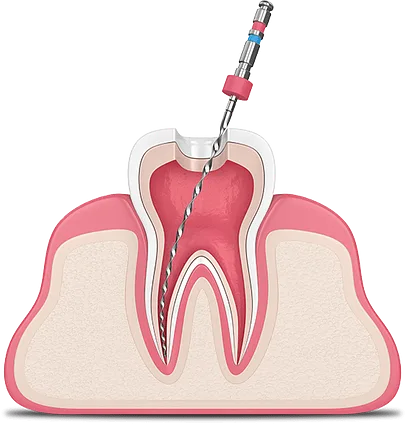

عصبکشی یا اندودنتیک یک روش درمانی است که برای درمان عفونت یا آسیب به عصب دندان (پالپ) انجام میشود. در این فرآیند، بافت آسیبدیده یا عفونی از داخل دندان خارج شده و فضای خالی با مواد مخصوص پر میشود. هدف از این درمان حفظ دندان و جلوگیری از نیاز به کشیدن آن است.

- مرحله سوم: دسترسی به پالپ

پس از بیحسی، پزشک با استفاده از ابزارهای مخصوص، به بافت پالپ دندان دسترسی پیدا میکند. این کار معمولاً از طریق ایجاد یک سوراخ کوچک در سطح دندان انجام میشود.

- مرحله چهارم: خارج کردن بافت آسیبدیده

در این مرحله، بافت پالپ آسیبدیده یا عفونی با استفاده از ابزارهای خاص خارج میشود. این کار باید با دقت انجام شود تا هیچ بخشی از بافت عفونی باقی نماند.

- مرحله پنجم: تمیز کردن کانالها

پس از خارج کردن بافت پالپ، کانالهای ریشه دندان تمیز و ضدعفونی میشوند. این کار برای جلوگیری از عفونتهای بعدی ضروری است.

- مرحله ششم: پر کردن کانالها

پس از تمیز کردن کانالها، آنها با مواد مخصوص پر میشوند تا فضای خالی پر شود و از ورود باکتریها جلوگیری شود. این مواد معمولاً از جنس گوتاپرکا هستند.